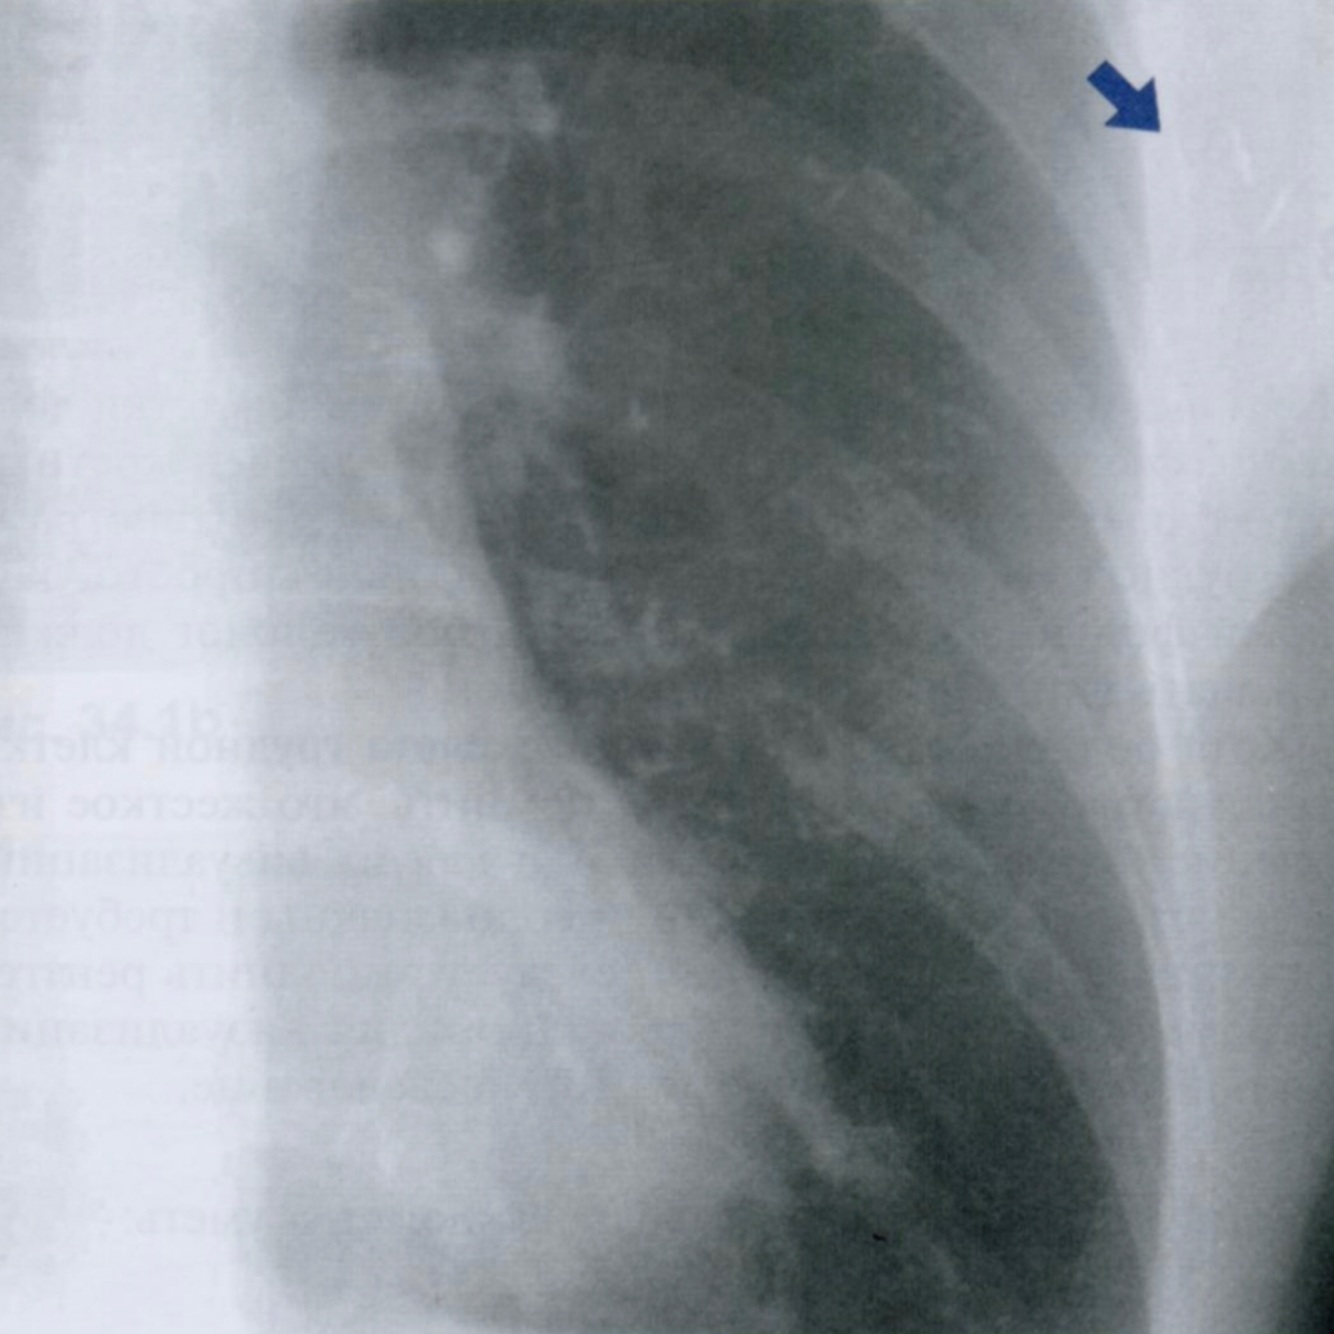

Данный снимок выполнен у одного и того же пожилого пациента с интервалом в 3 месяца. Обратите внимание на неравномерное утолщения ребер, отмеченные стрелками.

Дайте характеристику находке. Какие структуры грудной клетки наиболее часто поражаются?

Как отличить данную находку от костной мозоли после перелома?

Гематогенные метастазы - наиболее часто встречающиееся опухоли скелета грудной клетки у пожилых людей.

Особенно подозрительны кости, которые содержат костный мозг - ребра, грудина и позвоночник.

На повторном снимке мы видим прогрессию кортикального дефекта и увеличение размера метастаза.

На снимке слева ниже для сравнения показано веретенообразное утолщение после перелома ребра (костная мозоль), которое не сопровождается остеолическими изменениями кости. Важно визуально отличать костные мозоли и метастазы на ребрах.

На правом снимке также представлены участки остеолиза на телах грудных позвонков +/- снижение их высоты (отмечено стрелкой). При этом эти изменения не видны в ЗПП, поэтому показана БП.